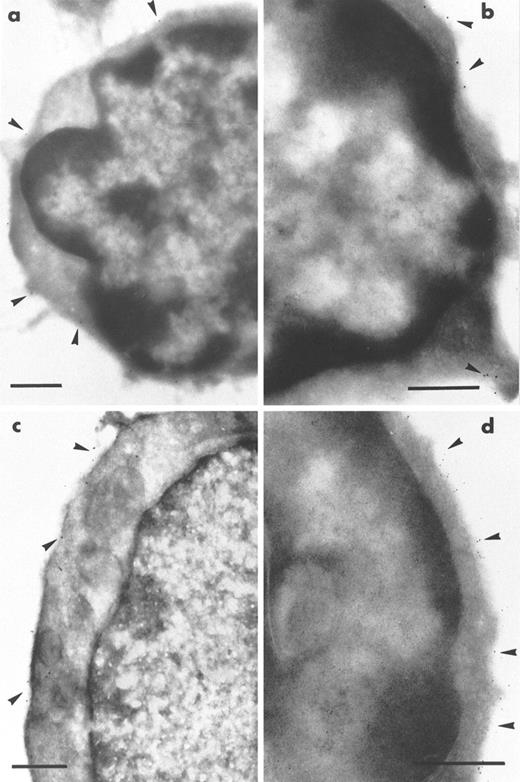

Immunogold staining of frozen ultrathin sections of marrow from MαIIb-tk mice was performed using MoAbs directed against immature hematopoietic markers such as anti-Sca-1 and anti-CD34. Among the mononuclear cells, we found that a population of small size (from 4 to 7 μm in diameter) with a high nucleus/cytoplasm ratio and a round nucleus with peripheral chromatin condensation were labeled with a MoAb directed against Sca-1 (Fig 2a). The labeling was present on the plasma membrane of the cells. Approximately 20% of the mononuclear cells were Sca-1+, a considerably higher percentage than in normal marrow, in which Sca-1+cells were extremely rare. It should be noted that the proportion of small mononuclear cells in the depleted mice corresponds to approximately 40% of the total bone marrow cell population. Therefore, it can be calculated that the proportion of Sca-1+ cells represents approximately 8% of the total depleted bone marrow cell population.

Immunogold labeling of ultrathin sections of cells remaining in the depleted bone marrow of the transgenic MIIb-tk mice after GCV treatment. Labeling was performed using rat MoAb to murine markers and bound IgG were shown by goat IgG coupled to gold particles. (a) A typical small Sca-1+ cell (4 to 7 μm diameter) with a high nucleus/cytoplasm ratio. Sca-1 labeling (arrowheads) is visible on the plasma membrane of the cell. (b) A CD34+cell labeled on the plasma membrane (arrowheads) also presents the morphological features of an immature cell. (c and d) Double-labeling for Sca-1 and CD45R. Sections were first incubated with MoAb directed against Sca-1 whose binding was shown by goat antibody to rat IgG coupled to 10-nm gold particles. After rapid fixation, sections were then incubated with MoAb directed against CD45R whose binding was shown by goat antibody to rat IgG coupled to 5-nm gold particles. An example of a Sca-1+ CD45R− cell is illustrated in (c). Only 10-nm gold particles (arrowheads) showing the presence of the Sca-1 antigen are present on the plasma membrane of this cell. In (d) is shown an example of a Sca-1− CD45+ cell present in the same preparation. The labeling is intense for CD45R and numerous 5-nm gold particles (arrowheads) are exclusively found associated with the plasma membrane of this cell. Bars = 0.5 μm.

The cellularity of these marrow samples was reduced to approximately 35% of the levels present in normal bone marow. Because the Sca-1+ cells expressed the morphological characteristics of immature cells, the presence of CD34 was also examined. CD34+ cells were present but were less abundant than those labeled for Sca-1+. As shown in Fig 2b, these cells exhibited similar morphological characteristics of primitive and immature cells. To assess the proportion of B lymphocytes in the population of Sca-1+ cells, double-staining was performed with an antibody against CD45R. We found that the majority of the Sca-1+ cells were negative for CD45R. A Sca-1+CD45R− cell is shown in Fig 2c. Only a few cells were found to be positive for both markers. The depleted bone marrow also contained a population of CD45R+ but Sca-1−cells, implying that the B-lymphocyte lineage was not affected by GCV treatment (Fig 2d). Overall, these results indicated that a majority of Sca-1+ cells did not belong to the B-lymphocyte lineage and that they presented characteristics of immature hematopoietic cells. Little labeling was seen using the MoAb anti-Thy-1 directed against T cells, thus excluding the possibility that the Sca-1 cells express high levels of this antigen (data not shown). All of these results suggest that a large proportion of the cells remaining in the depleted marrow correspond to immature hematopoietic cells.